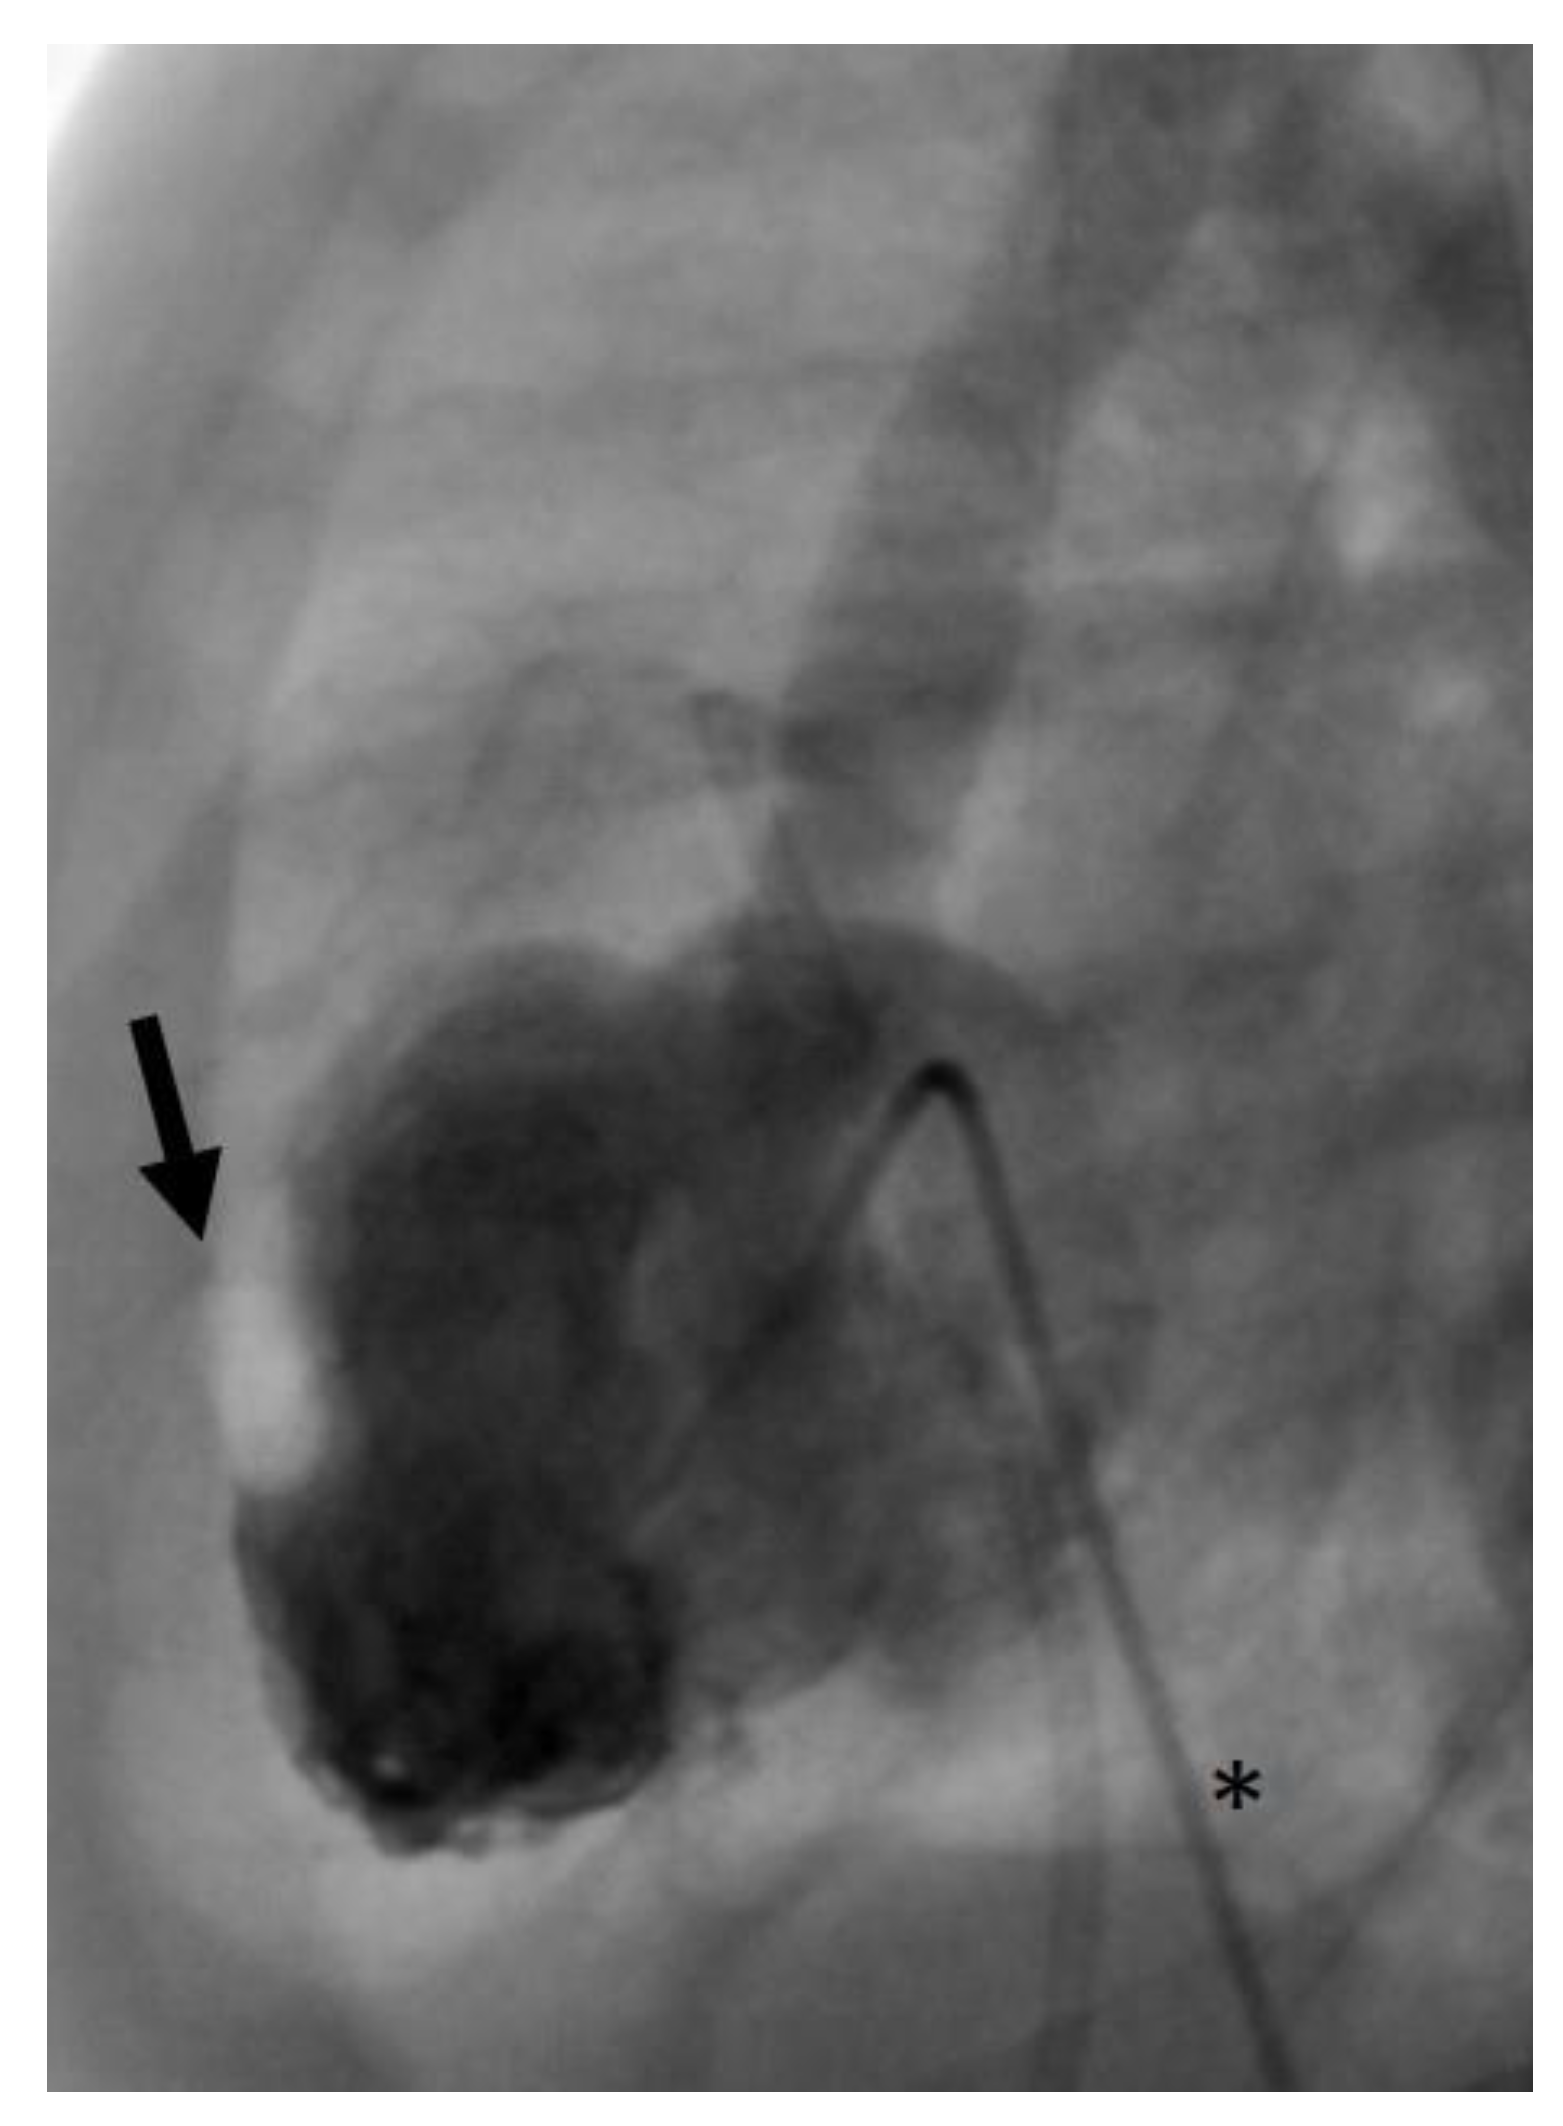

- In the same patient, an aortic wall injury resulting in a constriction of the intima following the second BAV occurred (Figure 9). However, this constriction was without significant stenosis and was corrected at the time of necessary aortic valve repair.